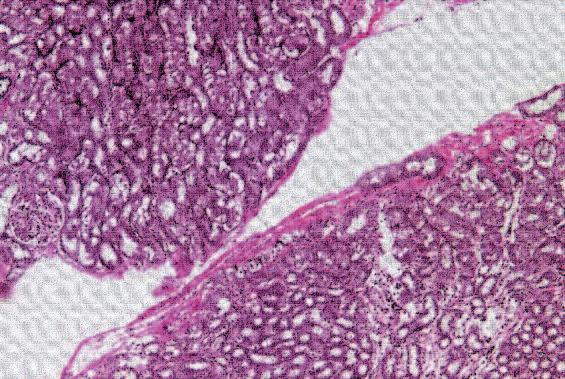

Nella figura A è possibile vedere la struttura del tessuto di un seno non predisposto per l’allattamento, caratterizzato dalla struttura densa di tessuto connettivo che circonda il condotto del latte, al centro dell'immagine, in gran parte chiuso.

In netto contrasto, la figura B mostra la struttura cellulare di un seno predisposto all’allattamento, caratterizzato da tessuto connettivo lasso, la presenza di cellule della ghiandola principale necessaria per la produzione di latte (piccoli cerchi bianchi), nonché il condotto del latte ampiamente aperto (al centro dell'immagine).

A. Condotto del latte (chiuso) nel tessuto del seno in condizioni normali

B. Condotto del latte (aperto) durante l’allattamento

A Ripresa di un condotto del latte al microscopio, sito in un seno non predisposto all’allattamento (chiuso)

B. In funzione dell’allattamento si ristruttura il tessuto mammario. Il condotto è aperto e il latte può uscire.

La foto nella pagina a fianco mostra una sezione trasversale al microscopio del fegato di un paziente con ‘leucemia linfatica’. Ciascuno dei piccoli puntini viola nella foto è un globulo bianco (in questo caso linfocita) che ha invaso il tessuto del fegato (aree rosa).

Considerando l’enorme quantità di questi puntini viola e il numero di enzimi che assimilano il collagene che ciascuno produce, è facile prevedere l’ingente distruzione del tessuto connettivo e il danno apportato all’organo da questo tipo di cancro.

Immagine al microscopio della leucemia linfatica

Globuli bianchi affetti di cancro (linfociti) invadono il fegato L’enorme quantità di collagenasi prodotte da queste cellule distruggono l’organo e causano insufficienza epatica.